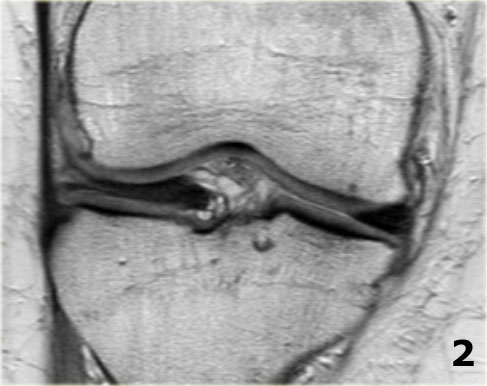

Hãy quan sát hình ảnh bên trái và cố gắng xác định vấn đề của sụn chêm này là gì.

Sau đó tiếp tục xem các hình ảnh liên tiếp tiếp theo của cùng bệnh nhân này.

Như bạn đã đoán được qua tiêu đề của đoạn này, đây là một trường hợp sụn chêm lật (flipped meniscus).

Sụn chêm lật là một dạng đặc biệt của rách dạng quai xô (bucket-handle tear).

Sụn chêm lật xảy ra khi mảnh vỡ của sừng sau bị lật ra phía trước, khiến sừng trước của sụn chêm có vẻ to hơn bình thường.